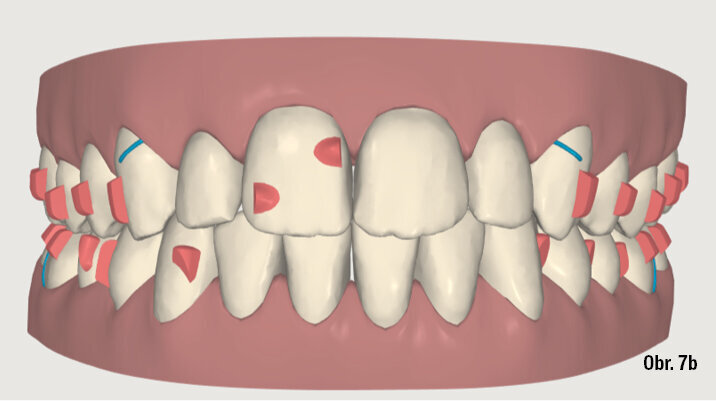

25letá pacientka požadovala estetickou ortodontickou léčbu, kterou nebylo jednoduché naplánovat vzhledem k tomu, že je umělkyní a cestuje po celé Evropě. Během vyšetření byla diagnostikována II. třída 1. oddělení, mírné stěsnání v dolní čelisti a středně těžké stěsnání v čelisti horní. Incizální schůdek byl 10 mm. Profilová zkouška jasně ukazuje protruzní postavení rtů (obr. 1a–c). Pacientka odmítla extrakční nebo ortodonticko-chirurgickou léčbu. Vhledem k jejím požadavkům na estetiku byl léčebný plán stanoven takto: léčba fóliovými aparáty Invisalign (Align Technology) s výsledným postavením molárů i špičáků v I. třídě, které bude dosaženo postupnou distalizací horních molárů s pomocí kompozitních attachmentů na všech distalizovaných zubech a tahů II. třídy (obr. 2, 3). Pacientce bylo doporučeno nosit fólie a tahy II. třídy nejméně 21 hodin denně. Dále pacientka používala přístroj AcceleDent 20 minut denně po celou dobu trvání ortodontické léčby. Fólie byly měněny každé 2 týdny, dokud nebyly druhé horní moláry plně distalizovány, potom každých 10 dnů, dokud nebyly první moláry ve své finální pozici, a nakonec každých sedm dní až do konce léčby.

ClinCheck (Align Technology) software navrhl k získání požadovaných výsledků 63 alignerů s předepsaným množstvím atachmentů a nasazením tahů II. třídy. Odhadovaná doba léčby byla přibližně 30 měsíců. Nicméně protože se pacientka rozhodla používat přístroj AcceleDent, léčba byla ukončena již po 18 měsících bez nutnosti refinementu, tedy s původně plánovanými 63 alignery (obr. 4a–c, 5a–c).

Klinický výsledek byl vynikající, postavení molárů i špičáků v I. třídě, vyhovující překus a předkus. I profil dolní třetiny obličeje byl výrazně lepší.

Na překrytí kefalometrických snímků je zřejmá distalizace molárů o 6 mm bez výraznějšího sklonu a s ideálním bukolingválním sklonem řezáků. Tahy druhé třídy umožnily protrakci mandibuly o 1,5 mm. Jako retenční aparáty jsme zvolili Vivera retainery (Align Technology) (obr. 6, 7a–c, 8a–c).